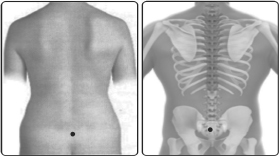

மூத்திரக்காலத்திற்கு நேர் பின்புறம் முதுகெலும்புத்தொடரில் அமைந்துள்ளதே சலப்பிற வர்மமாகும். இவ்வர்மம் ஜலப்பிற வர்மம், சடப்பிறக்காலம், சரடயந்த காலம் என்னும் வேறுபெயர்களாலும் வழங்கப்படுகிறது.

நீர்ப்பையில் பின்பாகம் எதிராக இருக்கின்ற வர்மம் சலப்பிறவர்மமாகும். இஃது தாங்கும் மாத்திரை அளவில் தாக்கம் கொண்டால் மலம், நீர் அடைத்துக்கொள்ளும். மாத்திரை மிஞ்சி தாக்கம் கொண்டால் இயங்கும் கை கால்களும் தளர்ந்து உடலும் தளரும். இதற்கு இதன் மாத்திரை அறிந்து தக்க கைபாகத்துடன் கூடி மருந்தும் செய்ய நலமடையும் என்பதாகும்.